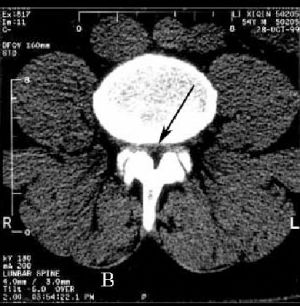

Стенозом позвоночного канала называют уменьшение его размера в передне-заднем направлении, а также уменьшение его ширины. Сужение позвоночного канала в поясничном отделе наиболее часто встречается при гипертрофии (увеличении) фасеточных суставов, желтой связки, уменьшении фораминального отверстия (места выхода нервного корешка из позвоночного канала) за счет разрастания остеофитов, изменении оси позвоночника (сколиоз, спондилолистез). (Рис.1,2А,В)